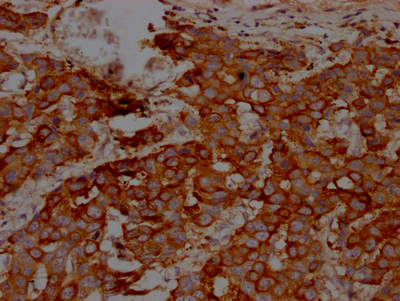

ApplicationELISA, WB, IHC, IF; Recommended dilution: WB:1:500-1:5000, IHC:1:50-1:200, IF:1:20-1:200